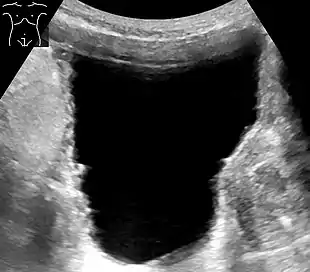

| Urinary retention with greatly enlarged bladder as seen by CT scan. | |

Analysis of urine flow may aid in establishing the type of micturition (urination) abnormality. Common findings, determined by ultrasound of the bladder, include a slow rate of flow, intermittent flow, and a large amount of urine retained in the bladder after urination. A normal test result should be 20-25 mL/s peak flow rate. A post-void residual urine greater than 50 ml is a significant amount of urine and increases the potential for recurring urinary tract infections. In adults older than 60 years, 50-100 ml of residual urine may remain after each voiding because of the decreased contractility of the detrusor muscle.[5] In chronic retention, ultrasound of the bladder may show massive increase in bladder capacity (normal capacity is 400-600 ml).